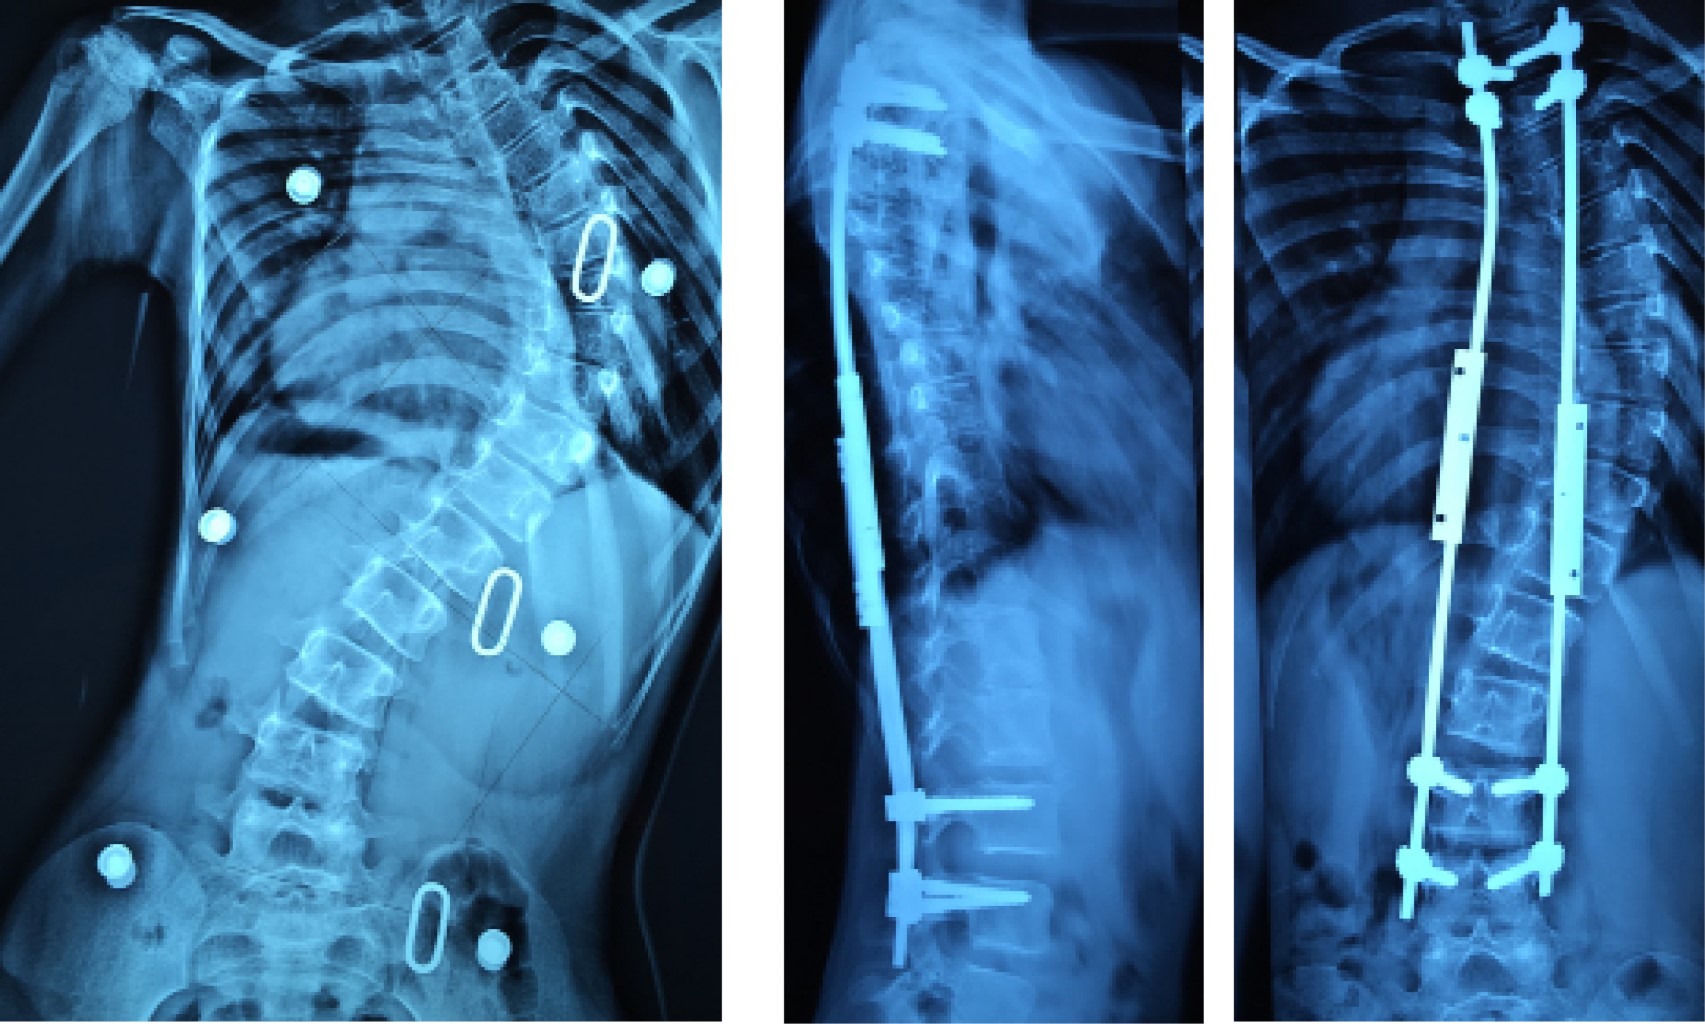

Como se ha mencionado anteriormente, los tratamientos deben estar enfocados a favorecer un crecimiento de la columna y tórax, así como un adecuado desarrollo pulmonar. Dentro de las opciones quirúrgicas aquellos tratamientos "amigables con el crecimiento" por si solos tienen una tasa de complicaciones cercana a 60%, por lo cual, realizarlos de forma temprana puede favorecer a resultados adversos desencadenando múltiples complicaciones dentro de las que destacan desde problemas cutáneos pasando por rupturas y desanclajes de los implantes, hasta autofusión de la columna. Bess y colaboradores en su estudio de las complicaciones en pacientes con EOS tratados con barras de crecimiento observaron que el riesgo de complicaciones disminuía 13% por cada año que el paciente fuera mayor al inicio del tratamiento (Figura 3).20

Figura 2

Figura 3